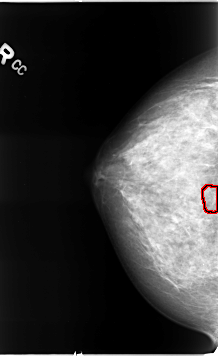

B_3079_1.RIGHT_CC

RIGHT_CC LINES 4624 PIXELS_PER_LINE 2832 BITS_PER_PIXEL 12 RESOLUTION 50 OVERLAY

FILE: B_3079_1.RIGHT_CC.OVERLAY

TOTAL_ABNORMALITIES 1

ABNORMALITY 1

LESION_TYPE CALCIFICATION TYPE PLEOMORPHIC DISTRIBUTION CLUSTERED

ASSESSMENT 4

SUBTLETY 4

PATHOLOGY MALIGNANT

TOTAL_OUTLINES 1

BOUNDARY